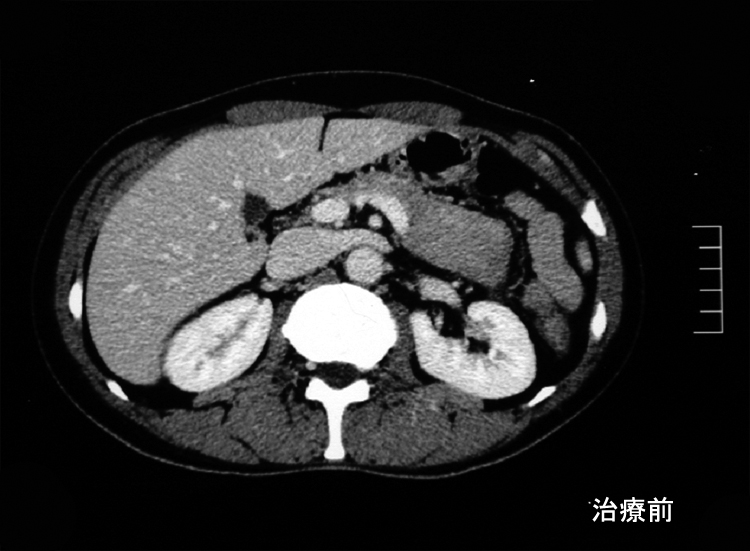

本性例のERCP画像では主膵管とその分枝にあきらかな狭窄所見や壁の不整を認めない。 膵には頭部(CT画像なし),尾部に腫瘤が形成されている。

腹腔内には静脈を巻き込むように血管周囲に腫瘤の形成がある。(クリックで大きな画像が見られます)

悪性リンパ腫や膵癌など悪性腫瘍は否定され自己免疫性膵炎と診断し, steroid治療を開始する。約2ヶ月の投与で, 膵、腹腔腫瘤は著明に縮小または消失しました。steroid減量中に黄疸が出現, 画像診断で硬化性胆管炎の合併をうたがいsteroidを増量、黄疸は消失。以後steroid をゆるやかに漸減し中止したが症状の再発はない。